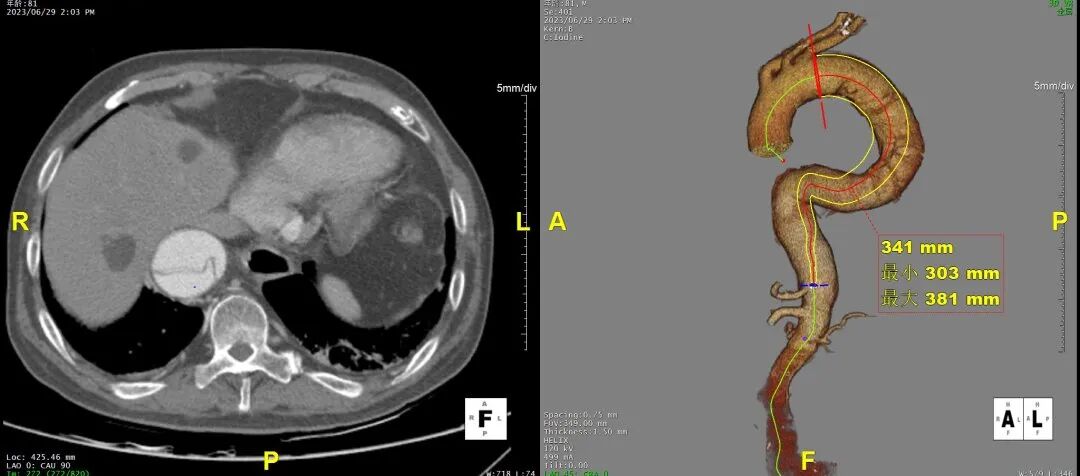

术前计划

• 支架覆膜起始部位定位于LSA后缘,远端定位于腹腔干上方60mm处,选择戈尔CTAG支架(TGU454520 + TGU343420),完成腔内隔绝,重塑真腔。

3)LSA起始部平均直径43mm+,降主段多发破口,真腔狭窄。